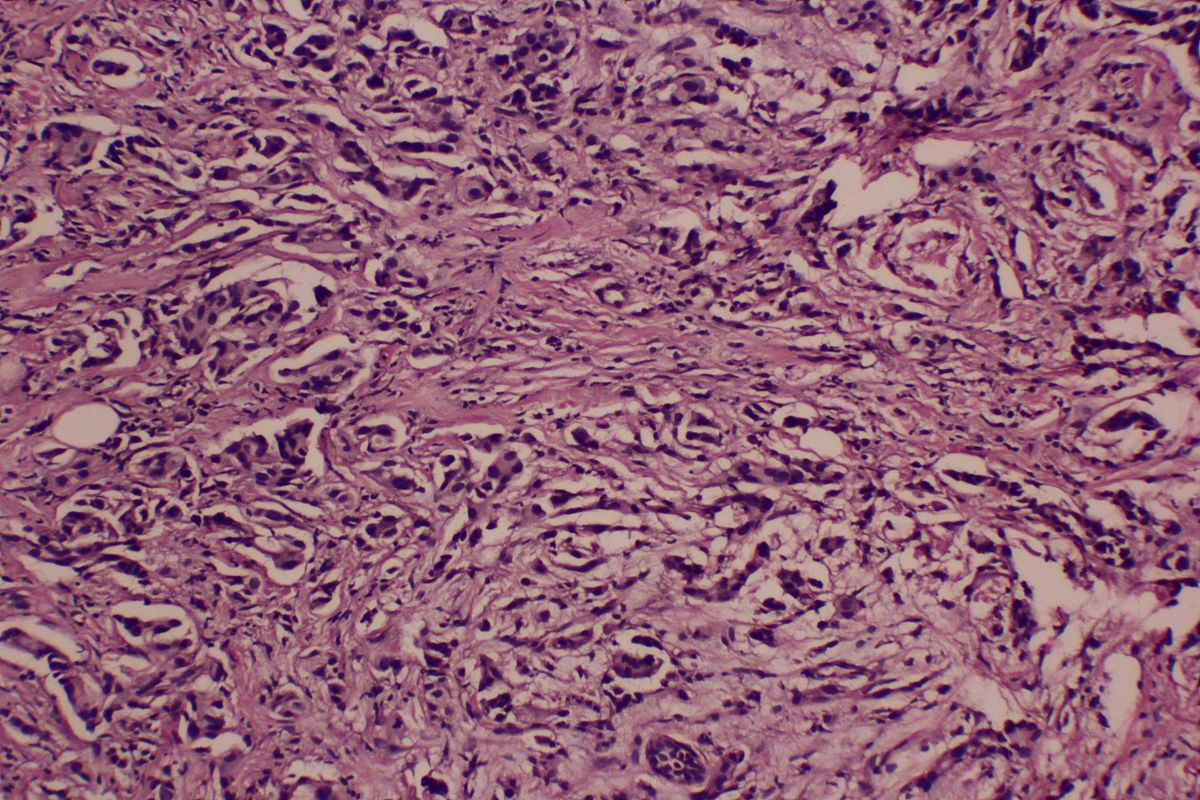

Dixon 수술 절제 샘플 : (직장) 돌출형 고분화선암 (Well differentiated adenocarcinoma), 점막 분비물 동반, 크기 5x3.5x15cm, 창자 벽까지 외막 섬유 지방 조직에 침투, 보관막 덮인 곳에서 피막을 뚫지 않음. 종양 내부 및 주변에 경도의 림프구 반응이 있으며, 신경 침범이 보임, 혈관암전은 보이지 않음. 종양 발아는 Bd1 (저등급 발아)임. 수술 최근 환상경계 및 추가로 제출된 (결합부근) (결합부원) 대장벽은 모두 깔끔함. 림프절 : 창자 주변 0/11 및 추가로 제출된 (253LN) 0/1에서 암 전이는 보이지 않음. IHC : CK20+++. HER-2 음성 (0), p53 ++. 미스매치 수리 단백질-pMMR : MLH1 핵+, MSH2 핵+, MSH6 핵+, PMS2 핵+. PD-L1 : CPS < 1 (분석 방법 : 면역 조직 화학, E1L3N 클론, VENTANA BenchMark GX에서 편도 혈관 내피 세포와 섬유 세포를 음성 대조로 사용 : 편도 융기 상피는 강 양성 대조, 편도 림프 덩어리 생발 중심의 거대 세포는 약한 양성 대조)

病理诊断Dixon术切除标本直肠隆起型高分化腺癌Well differentiatedadenocarcinoma伴产粘液大小5x35x15cm浸润肠壁达外膜纤维脂肪组织有浆膜被覆处未突破间皮层。肿瘤内部及周边轻度淋巴细胞反应可见神经侵犯未见脉管癌栓。肿瘤出芽为Bd1低级别出芽。手术最近环周切缘及另送吻合口近端、吻合口远端大肠壁均净。淋巴结肠周011及另送253LN01未见癌转移。IHCCK20+